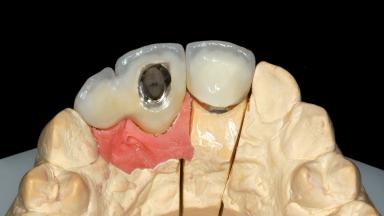

Prosthesis Type FDP

Defining Characteristics One missing tooth to be replaced by an implant-borne crown

Loading Protocol Conventional or early

Retention Cemented, with prosthesis margin < 3mm submucosal Cemented, with prosthesis margin < 3mm submucosal